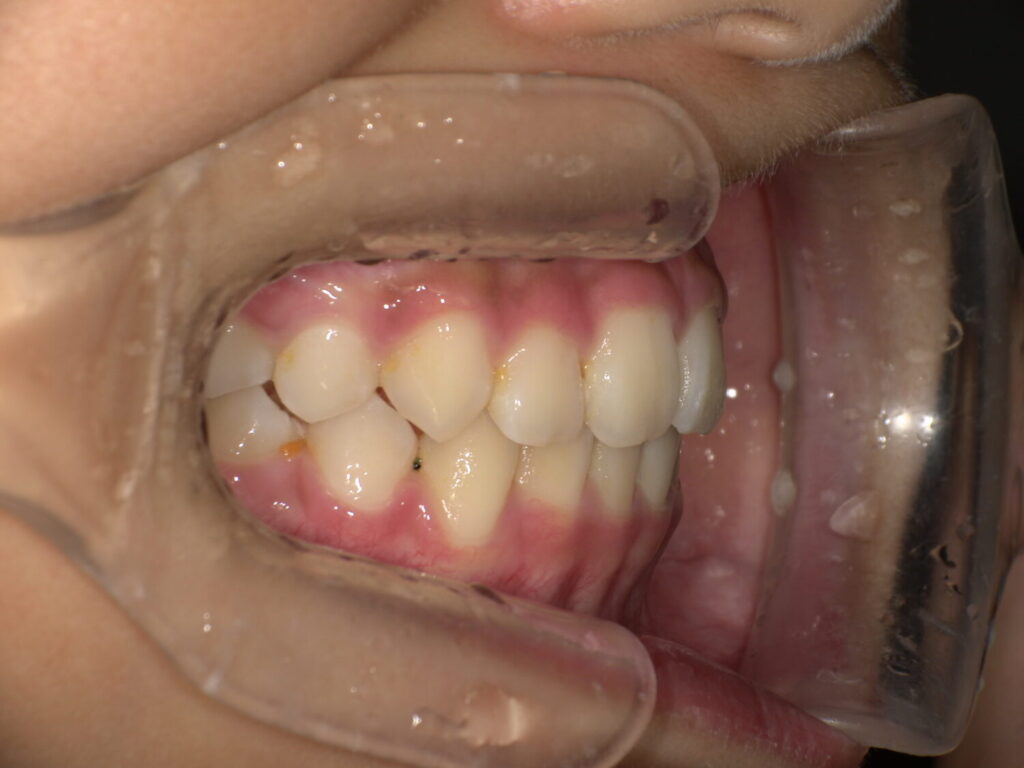

一年後の経過

前歯も生えてきたのですが2番目の歯の隙間はなく後ろから生えてきています。

ですがこれはマウスピースとアクティビティーでここまで綺麗に入りました。

2回目の装置セット

もう少し顎を前にしたいので、2回同じ装置を装着しました。

マウスピースの併用も大切です!

今はしっかり綺麗な噛み合わせになっています。